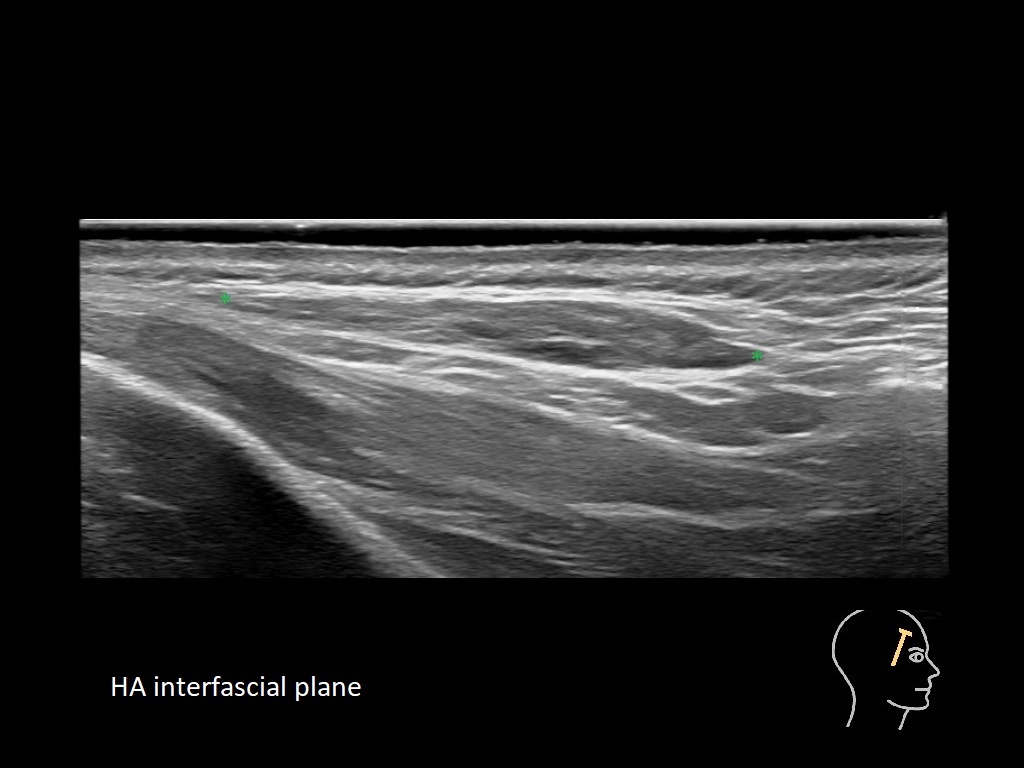

Draw in the image on the right where the fillers are located. To check if your answer is correct, please click on the secondary image.